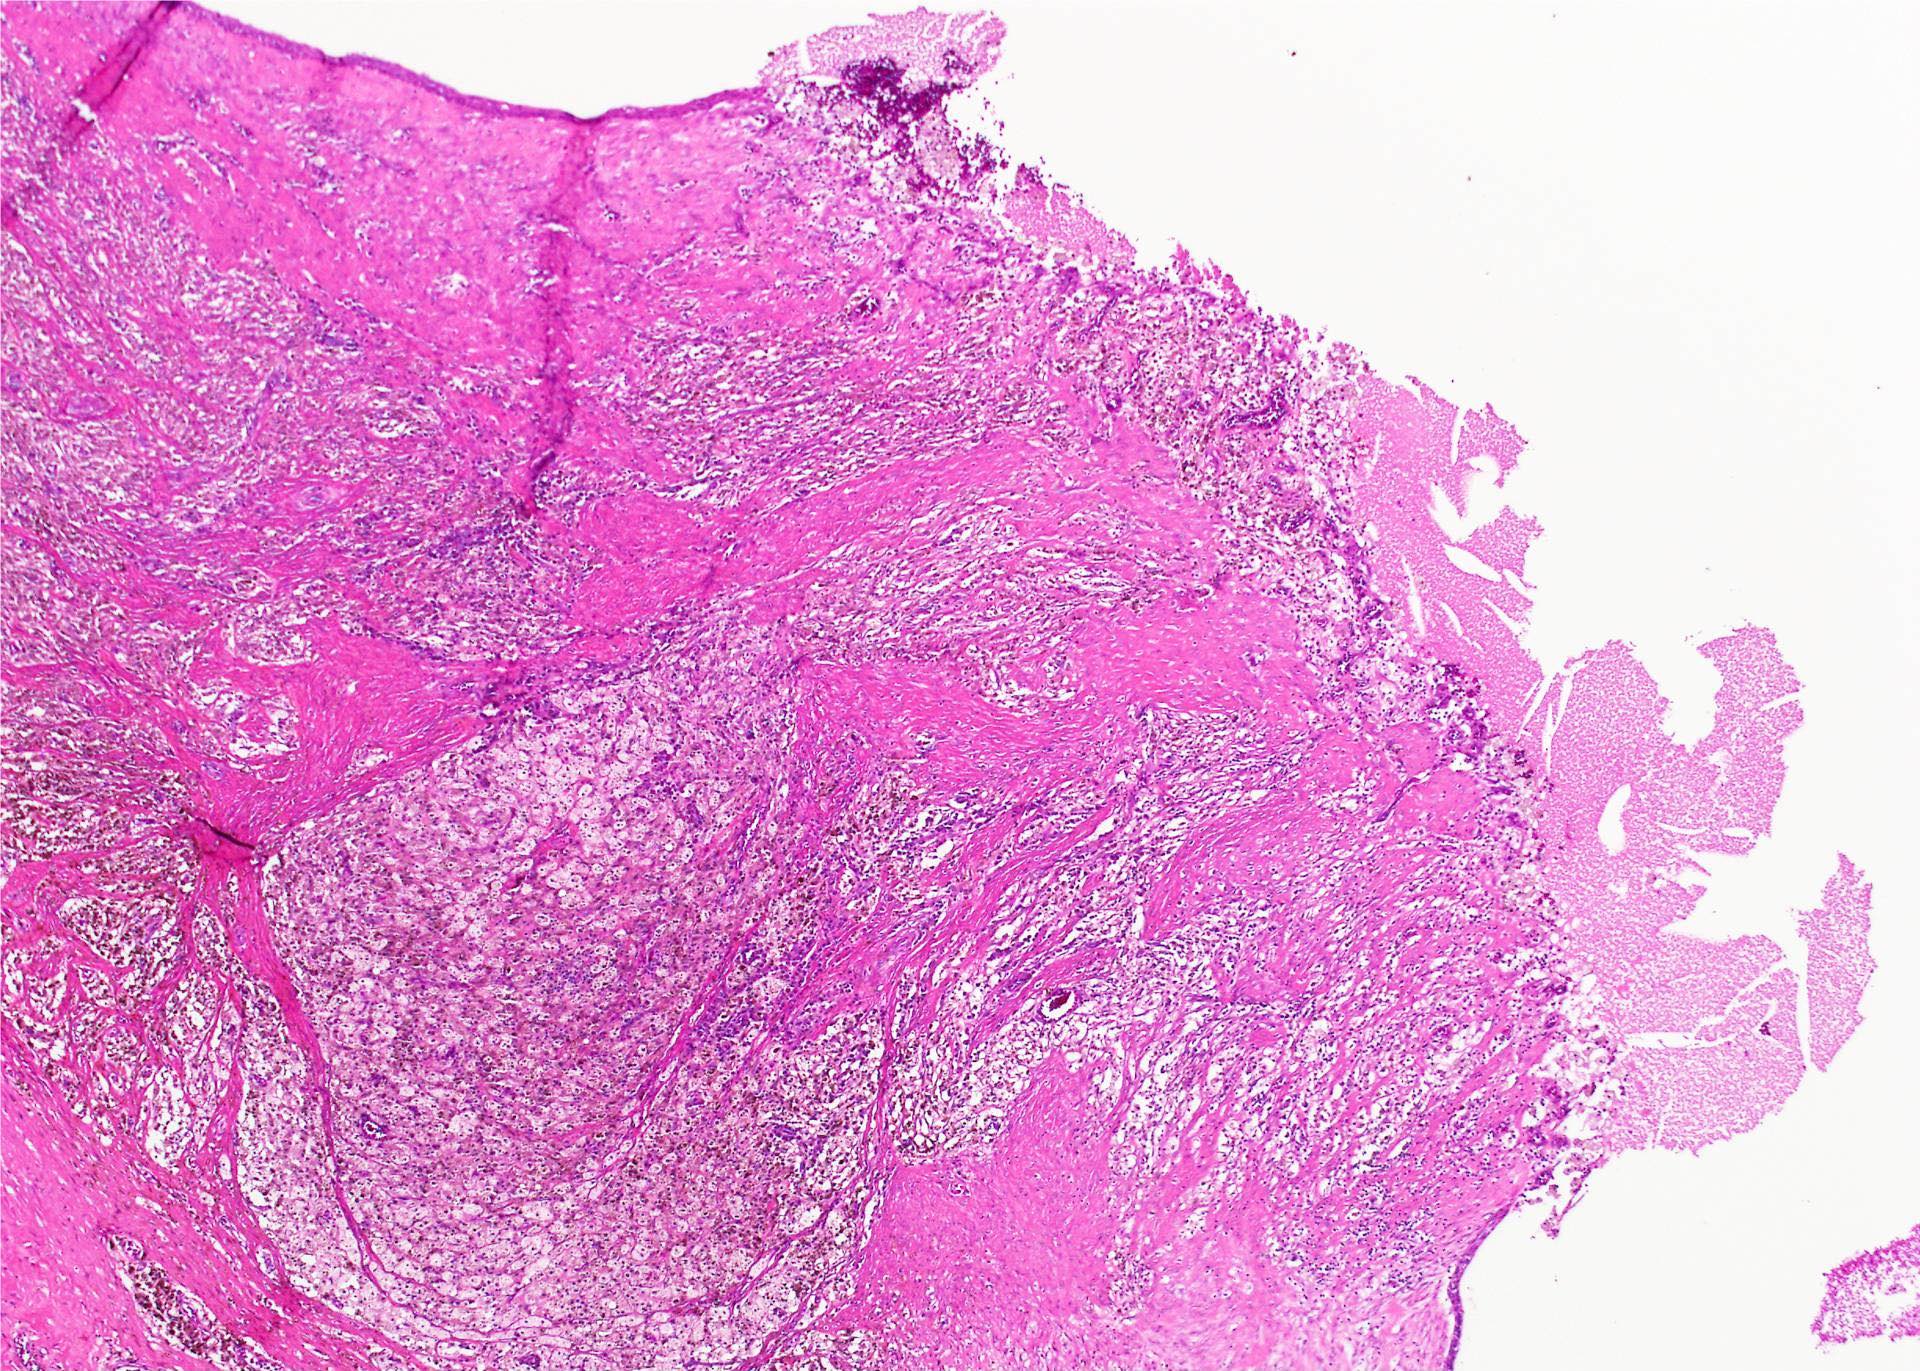

Microscopic (histologic) description

- Type of epithelial lining varies by site, and combinations of the types below can be seen in a single cyst (Head Neck Pathol 2013;7:50):

- Very often the cyst is denuded of epithelium, at least focally, which reflects epithelial damage by inflammation

- Secondary inflammation is common, especially in sinus tract (J Pediatr Surg 1984;19:506):

- Intense lymphocytic infiltration, rarely arranged into lymphoid follicles

- Admixture of neutrophils (if the cyst is infected)

- Granulation tissue and fibrosis

Microscopic (histologic) images

Contributed by Andrey Bychkov, M.D., Ph.D., Mark R. Wick, M.D. and AFIP